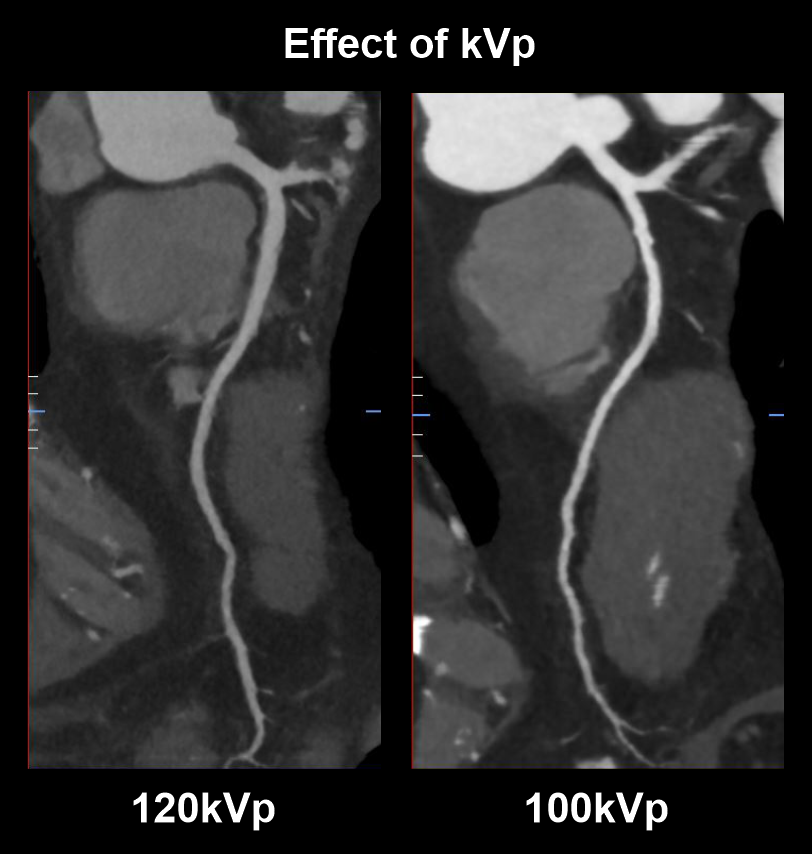

- Use 100 kVp with automated tube current modulation for patients ≤ 100 kg (non-obese).

Explanation: use of lower tube voltage (kVp) in patients with lower BMI provides satisfactory vascular contrast enhancement with slower flow rates and lower radiation dose. Although, over reduction of kVp might lead to poor image quality (high noise).

As in the diagram, scan with lower tube voltage (100kVp) has higher vascularcontrast than the scan with higher tube voltage (120kVp).